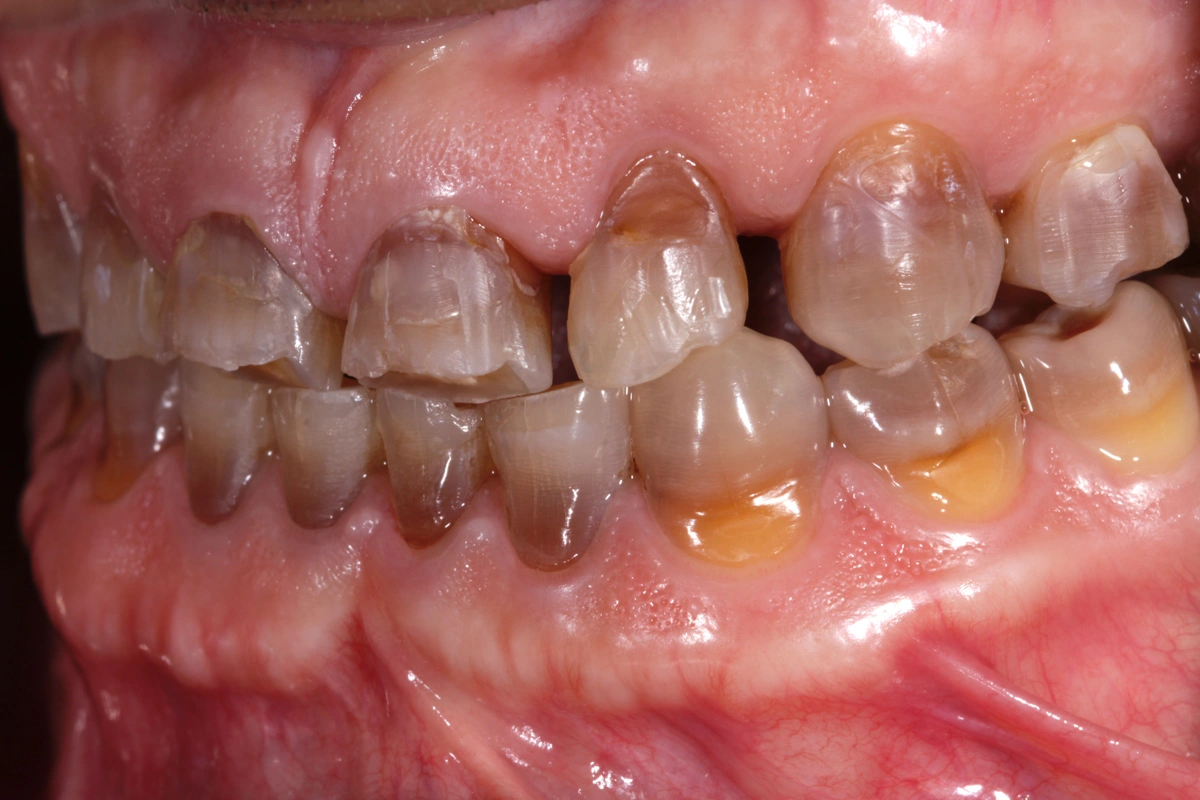

Paciente joven acude a consulta referido por el ortodoncista para tratamiento de desgaste.

La tetraciclina era un medicamento que se administraba en los años 50 que a posteriori se han podido observar los efectos secundarios que tienen en la boca: tinción dental intrínseca. Existen distintos grados y en función de su severidad. Las tinciones por tetraciclinas suponen un reto a nivel restaurador.

En este caso se trata de un paciente con desgaste dental severo y tinción por tetraciclinas grado IV.